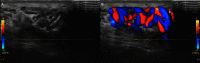

Fig. 2

A. Varicocele. B. Regurgitation during the Valsalva maneuver in color Doppler